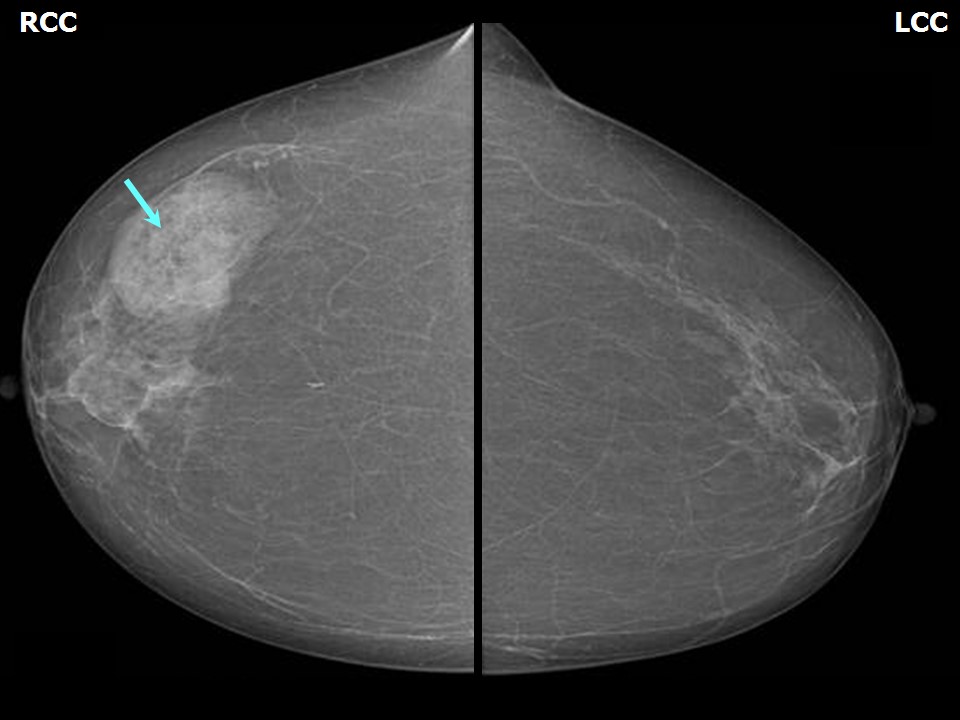

Феномен гипердиагностики в маммографии: примеры и иллюстрации

Раздел: Образы вокруг